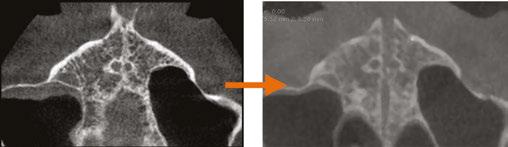

Drs. Claudia Pinter and Stanley Liu illustrate a protocol to improve nasal breathing in orthodontic care 31